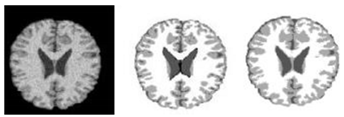

2.2. Segmentation of Brain Regions

2.2.1. Related-Work to the Segmentation of Brain Regions